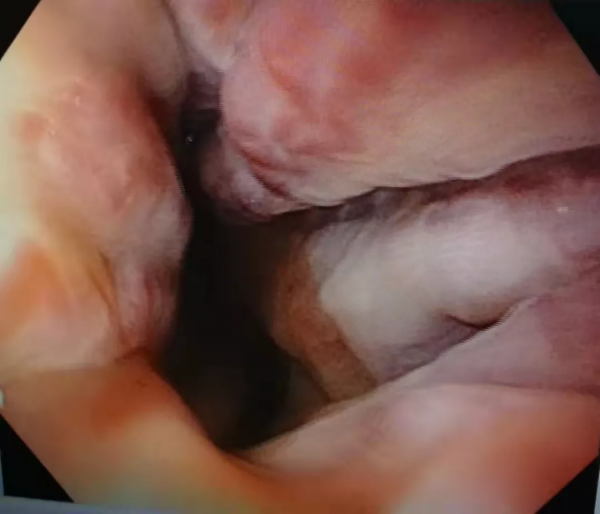

李阿姨今年70歲,查出肝硬化失代償期5年。這幾年她多次住院,子女們也是盡心盡力,都照顧的很好,從來沒有放棄過對她所患疾病的治療。前段時間因肝功能異常、腹水住院治療,期間查胃鏡提示:食管靜脈曲張(重度)。如下圖:

重度曲張的靜脈突向食管腔內